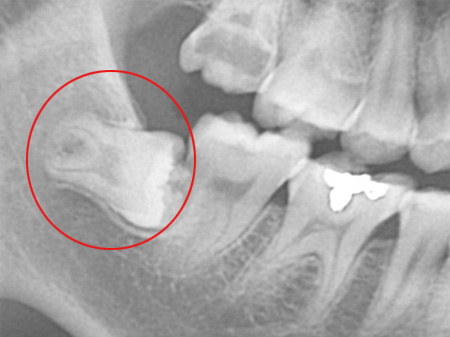

¸Åº¹ »ç¶û´Ï´Â ÅλÀ¿¡ °ø°£ÀÌ ÃæºÐÇÏÁö ¾Ê¾Æ »ç¶û´Ï°¡ ÀÕ¸öÀ» ¶Õ°í ¸ÍÃâµÇÁö ¸øÇϰí Ä¡Á¶°ñ ³»¿¡ ¸Åº¹µÈ °ÍÀ» ¸»ÇÕ´Ï´Ù. ÀÌ ¸Åº¹»ç¶û´Ï´Â Ä¡¾Æ°¡ ¿ÏÀüÈ÷ ¸ÍÃâµÇÁö ¾Ê¾Ò±â ¶§¹®¿¡ À½½Ä¹°ÀÌ »ç¶û´Ï ÀÕ¸ö ÇϹæÀ¸·Î °íÀÌ°Ô µÇ°í, Ä©¼ÖÁú·Îµµ Á¦´ë·Î Á¦°ÅµÇÁö ¾Ê¾Æ ÀÕ¸ö ¿°ÁõÀ» À¯¹ßÇÏ¿© »ç¶û´Ï´Â ¹°·Ð ÀÎÁ¢Ä¡¾Æ¿¡±îÁö ¼Õ»óÀ» ÀÔÈú ¼ö ÀÖ½À´Ï´Ù.

ÀÌ ¶§¹®¿¡ ¸Åº¹ »ç¶û´Ï´Â ¹ßÄ¡¸¦ ÇÏ´Â °ÍÀÌ °¡Àå ÁÁ½À´Ï´Ù. ´õÁÁÀº¼¿ïÄ¡°ú¿¡¼´Â ¿¢½º·¹ÀÌ Àåºñ, ÷´Ü CT µî´Â »ç¶û´Ï ¹ßÄ¡ Áø´Ü¿¡ ÇÊ¿äÇÑ Ã·´Ü Àåºñ¸¦ º¸À¯Çϰí ÀÖ¾î ¾ÈÀüÇÑ »ç¶û´Ï ¹ßÄ¡°¡ °¡´ÉÇÑ °ÍÀº ¹°·Ð ÀÓ»ó°æÇèÀÌ Ç³ºÎÇϱ⠶§¹®¿¡ ¾ÈÀüÇÏ°Ô »ç¶û´Ï ¹ßÄ¡¸¦ ¹ÞÀ¸½Ç ¼ö ÀÖ½À´Ï´Ù.